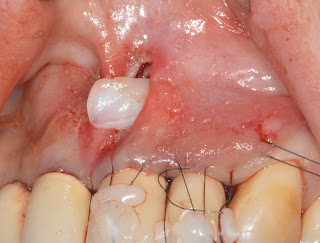

FGG for increasing vestibular depth and peri-implant keratinized mucosa during 2nd Surgery

3 wks later